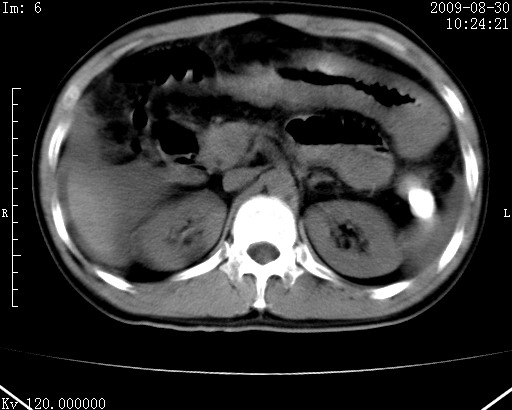

患者唐某,男31岁,已婚,本地务农。

自述入院前两天一次进食较多冷饮之后,出现阵发性上腹部疼痛,次日加剧伴恶心、呕吐,呕吐后症状稍减轻。食欲差。大便每天1-2次,量少,暗红色水样。小便赤。无畏寒、发热、咳嗽等呼吸道症状。无高血压及胃病史。

检查:体温、血压及脉搏正常.皮肤无黄染,浅表无淋巴结肿大。左腹肌紧张,左上腹有压痛,无反跳痛,可触及包块。

生化:钾、钠、氯、钙、ph正常,总胆红素和直接胆红素稍高,空腹血糖稍高。

尿淀粉酶:1256 u/l(正常60-401)。

血常规:wbc 22.4x109/l gr88% ly9.6%其余基本正常。

胃镜:急性胃炎。立位腹平片:未见异常。

下面是ct平扫,降结肠内是对比剂。

术前影像诊断:上段空肠急性缺血性坏死并腹水。建议手术治疗。

术中见上段空肠约70cm长范围坏死,从屈氏韧带远端约10cm处开始。坏死肠管肿胀变形变色,管壁明显环形增厚,部分聚成大肿块,无扭转和套叠。肠系膜上动脉分支内广泛泥沙状血栓。肠切除。

临床诊断:肠系膜上动脉梗塞并急性肠坏死。

开始时我们科也有人认为是套叠,最后统一意见,不考虑肠套。我们看到的“靶征”,“晕圈征”,“双圈征”实际上只是单根肠管的横断面。坏死肿胀后肠壁各层的密度不一样。

左侧腹小肠腔管壁明显增厚,部分内示靶征,走行异常,部分肠系膜绳样改变,肝包膜下及肠间较多液体密度,然梗阻近端肠腔积气不明显。

考虑;肠扭曲伴肠坏死。